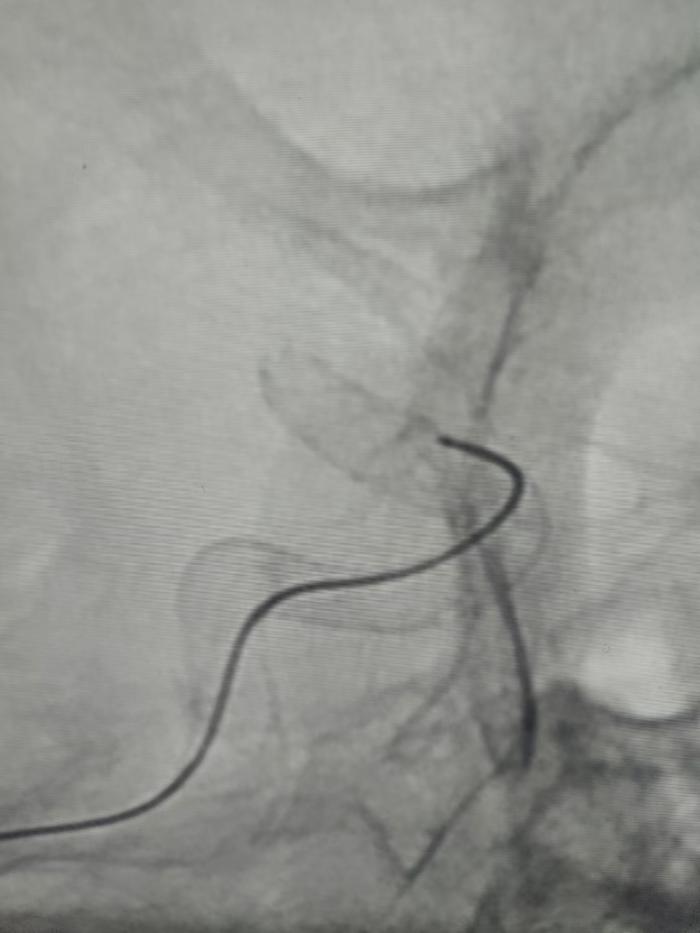

关键时刻,神经介入团队将目光投向了新型血流导向装置 —— 密网支架。这种直径仅5mm的精密器械,成为破局的关键。手术台上,主刀医生通过微导管将密网支架精准送入载瘤动脉,当支架如花瓣般展开的瞬间,它的“特殊技能”开始发挥作用。30%-35%的高金属覆盖率如同一张细密的防护网,不仅将动脉瘤与正常血流隔绝,更像一位“智能管家”引导血流重新规划路径。“传统支架的金属覆盖率只有5%-7%,就像用稀网捕鱼,而密网支架如同编织了一张坚固的渔网,既能拦住‘危险的鱼’,又能让‘水流’顺畅通过。”科主任陈雁斌打了个形象的比方。

这种革新不仅体现在物理屏障上。术后第三天的造影显示,载瘤动脉已恢复通畅,动脉瘤内开始形成血栓——这正是密网支架的 “生物魔法”。一方面,高达85% 的血流导向效率,让原本冲击动脉瘤的高速血流被温柔“引流”;另一方面,支架表面加速 30% 的内皮化进程,促使动脉瘤逐渐闭合。“过去我们靠填塞弹簧圈‘堵’住动脉瘤,现在是让血管自己‘长’好,就像园丁不再用木桩支撑歪树,而是引导根系自己扎稳。” 曾维军解释道。